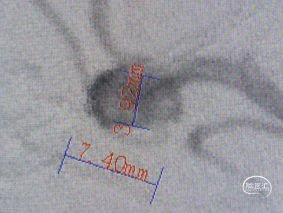

直接测量:7.4x3.92mm

3D测量:7.22x5.35mm

对比测量:8.9x4.8mm(偏大10%)